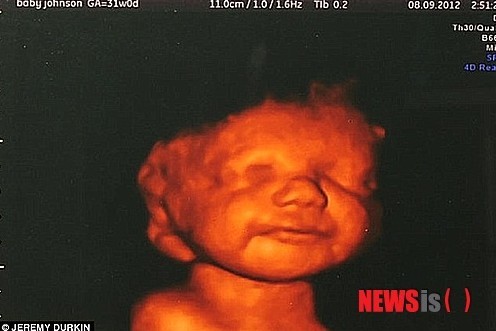

낙태와 관련한 가슴 아픈 세상의 모습과는 정반대의 기사가 올라왔다. 영국의 한 임산부(케이티아 로웨, 26세)에 대한 이야기다. 그 여성은 아이에게 심각한 장애가 추정돼 낙태시키는 것이 바람직하다는 의사의 권고에도 불구하고 아이를 출산했다. 이유는 너무나도 단순했다. 초음파 검사를 통해 미소 짓는 태아의 모습을 보고 아이 출산을 결심했다는 것이다.